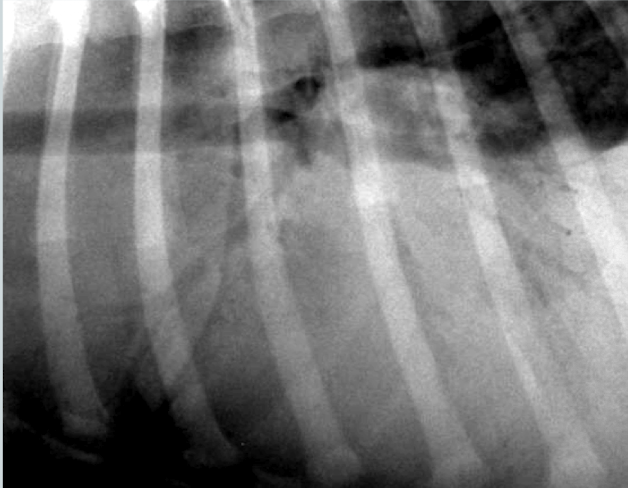

What lung pattern? What is the arrow pointing to?

Alveolar pattern

lobar sign

What is the likely condition? What are the arrows pointing to?

Aspiration pneumonia (bc right middle)

red: air bronchogram

blue: border effacement

yellow: lobar sign